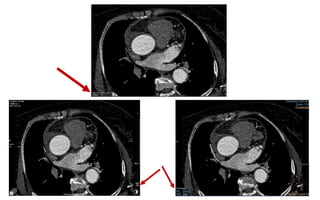

Single-source 64-slice CT with half-scan reconstruction resulting in

temporal resolution of 165 ms and dual-source 64-slice CT with half-scan

reconstruction resulting in temporal resolution of 83 ms .

Temporal Resolution

 Temporal resolution is still the major limitation of coronary CT and the main

cause of non diagnostic images, and therefore all possible measures must be

taken to improve this parameter.

 CT requires at least 180° plus fan angle of projection data to perform image

reconstruction.

 This implies that the intrinsic temporal resolution of a standard CT scan is in

the order of gantry rotation time /2.

 The temporal resolution is most dependent on the speed of the gantry

rotation.